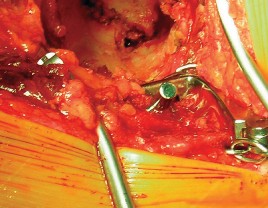

الخلاصة الطبية الشاملة: يُعتبر طول عمر مكون الحُق الأسمنتي في مفصل الورك الصناعي حجر الزاوية لنجاح جراحة استبدال مفصل الورك الكلي. يعتمد هذا النجاح بشكل كبير على التخطيط الدقيق قبل الجراحة، والتغطية الكافية من عظم المريض السليم، والتثبيت الأمثل للمكون بتقنيات أسمنتية حديثة. تتضمن الجراحة تقييمًا معمقًا لجودة العظم، إزالة دقيقة للنتوءات العظمية، وتطبيق مادة الأسمنت الطبي الحيوي لضمان تثبيت قوي ومستقر للحُق، مما يكفل الاستقرار والديمومة طويلة الأمد للمفصل الصناعي. مع المتابعة الدورية والالتزام بالبرنامج التأهيلي، يمكن للمرضى التمتع بنتائج ممتازة ونوعية حياة محسنة لسنوات عديدة. في صنعاء، يبرز الأستاذ الدكتور محمد هطيف كخبير رائد في هذا المجال، حيث يجمع بين الخبرة العميقة والتقنيات المتطورة لتقديم أفضل رعاية جراحية.

تُعد جراحة استبدال مفصل الورك الكلي (Total Hip Replacement - THR) من الإجراءات الجراحية الرائدة التي أحدثت ثورة في علاج آلام الورك المزمنة وتحسين القدرة الحركية للملايين حول العالم. ضمن هذا الإجراء المعقد، يلعب "مكون الحُق الأسمنتي" (Cemented Acetabular Component) دوراً محورياً في تحقيق الاستقرار والديمومة للمفصل الصناعي. إن تحقيق "طول عمر مكون الحُق الأسمنتي" ليس مجرد هدف تقني، بل هو وعد للمريض بحياة خالية من الألم، مليئة بالنشاط، وذات جودة عالية لسنوات طويلة بعد الجراحة.

في جراحة استبدال مفصل الورك الكلي، يتم استبدال رأس عظم الفخذ التالف بمكون معدني كروي، ويتم استبدال الحُق الطبيعي المتضرر بمكون حُقي صناعي. المكون الحُقي الأسمنتي هو عبارة عن كوب معدني أو بلاستيكي عالي الجودة (عادة من البولي إيثيلين) يتم تثبيته داخل تجويف الحُق في عظم الحوض باستخدام "الأسمنت العظمي" (Bone Cement)، وهو مادة بوليمرية حيوية تعمل كغراء قوي لتثبيت المكون بشكل فوري ومستقر.